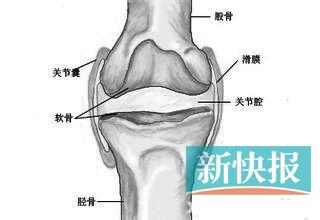

膝关节骨刺、滑膜炎、半月板损伤

病情分析:膝关节半月板损伤是一种以膝关节局限性疼痛,部分患者有打软腿或膝关节交锁现象,股四头肌萎缩,膝关节间隙固定的局限性压痛为主要表现的疾病。半月板损伤多由

膝盖半月板损伤怎么办半月板是膝关节2个月牙形的纤维软骨,位于胫骨平台内侧和外侧的关节面。其横断面呈三角形,外厚内薄,主要起到传递负荷和弹性缓冲的作用。半月板破

简介:半月板损伤(meniscus injury)是膝部最常见的损伤之一,多见于青壮年,男性多于女性。国外报道内、外侧半月板